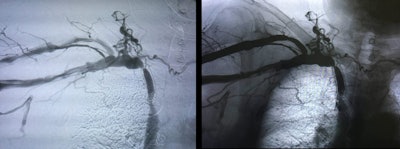

A typical venous therapy is, for example, one we use on young men who have impaired fertility. The cause of this condition is dilated veins in the testicles and kidneys. Interventionally, we do it in such a way that we embolize these vein clusters and thereby restore the fertility of these -- quite often -- young men. We also remove foreign bodies from veins. To do this, we use instruments such as pliers, wires, and drum/barrel devices.